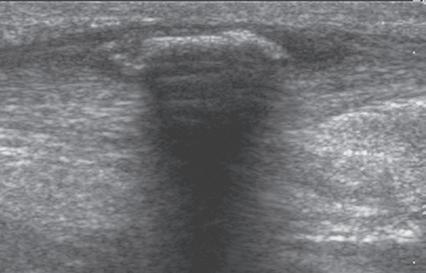

involved interface. Examples of structures that produce shadowing include interfaces with bone or calcification (Fig. 1.14), some foreign bodies (see Chapter 2), and gas. An object with a small radius of curvature or a rough surface will display a clean shadow, whereas an object with a large radius of curvature and a smooth surface will display a dirty shadow (resulting from superimposed reverberation echoes).8 Refractile shadowing may also occur at the edge of some structures, such as a foreign body or the end of a torn Achilles or patellar tendon (Fig. 1.15).9

Another important artifact is shadowing. This occurs when the ultrasound beam is reflected, absorbed, or refracted.7 The resulting image shows an anechoic area that extends deep from the